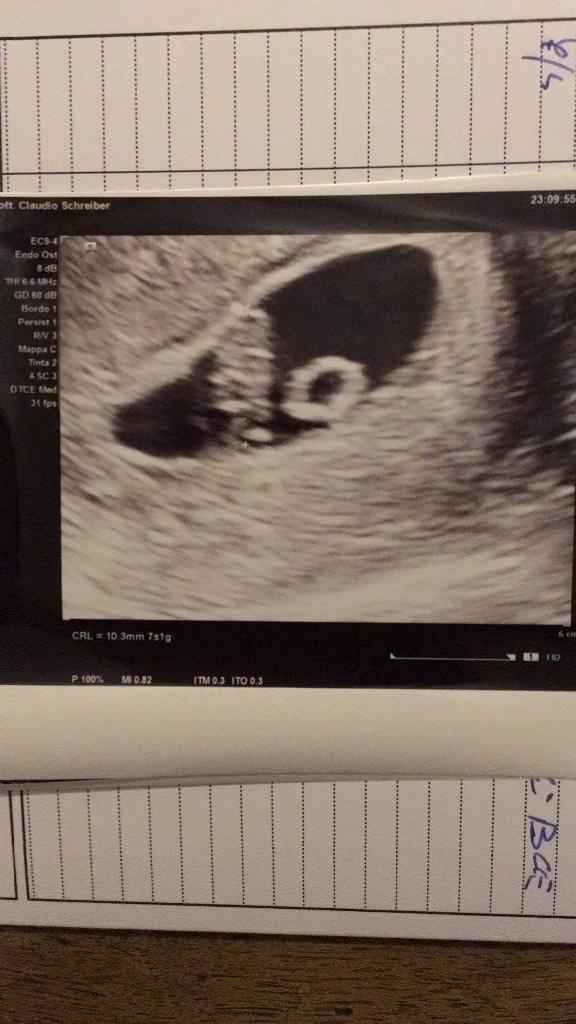

Pubblicato in Future mamme 48